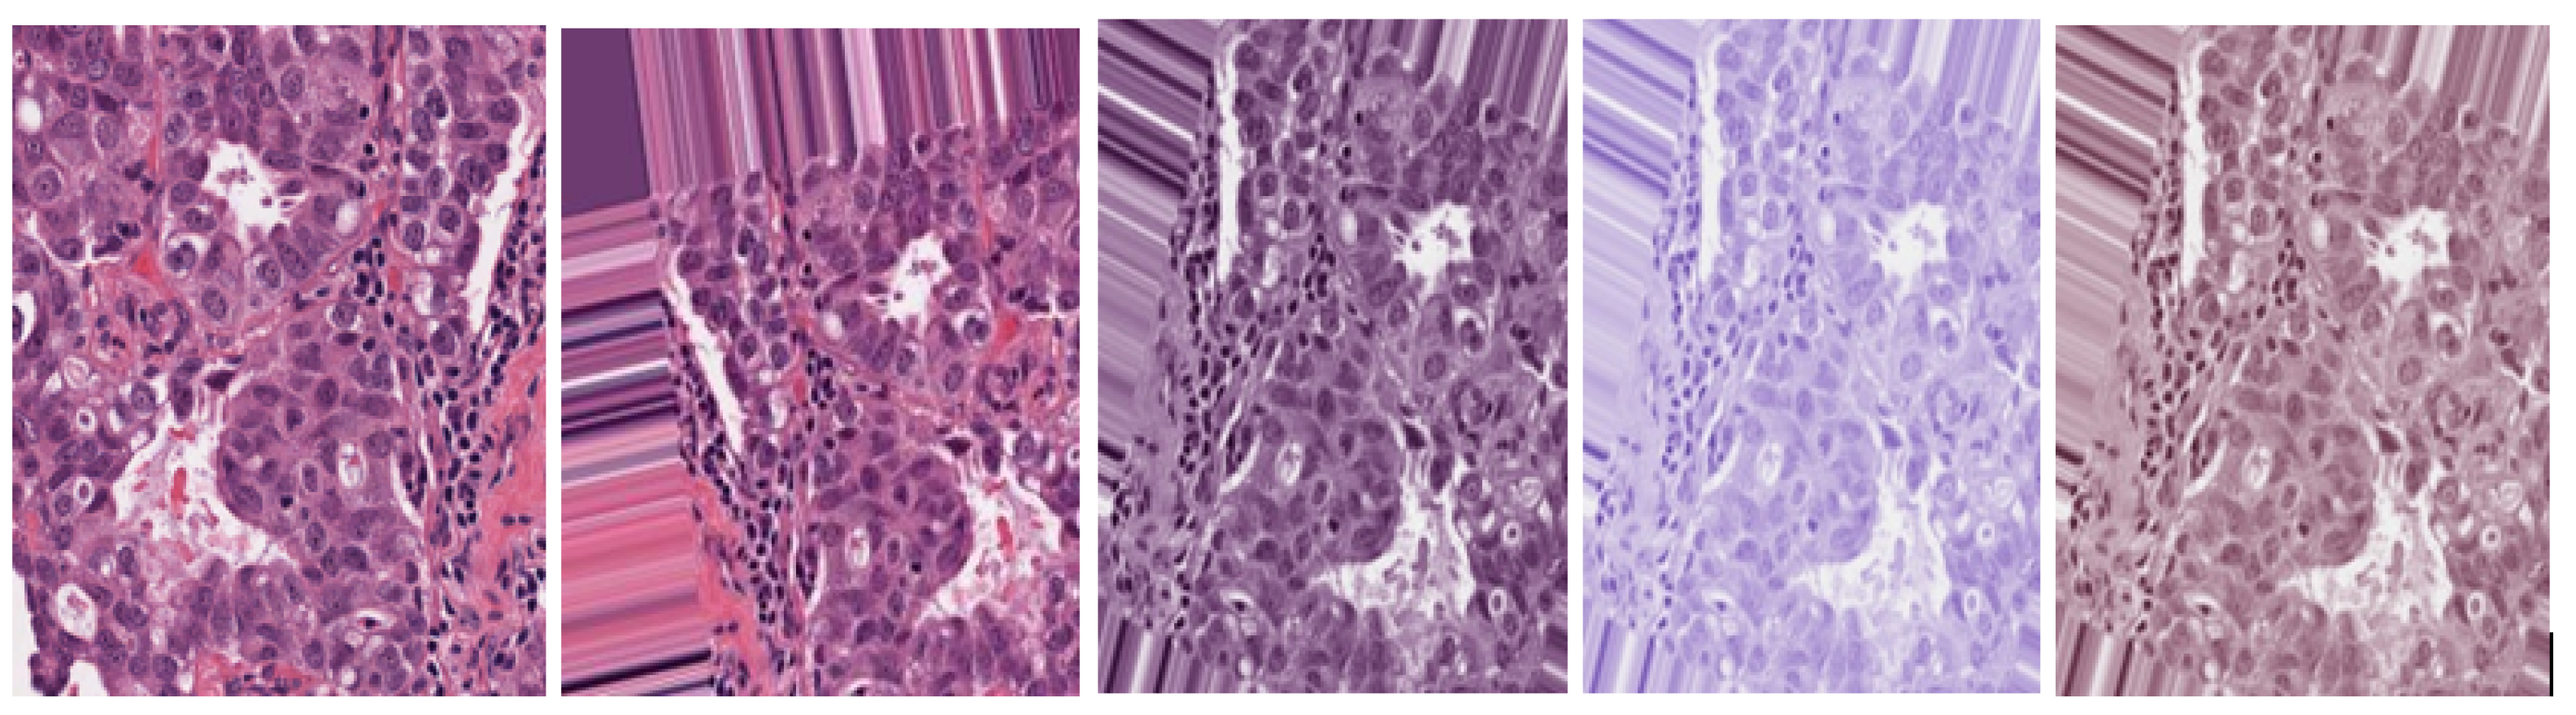

- Augmentation methods are used to deal with data scarcity. Additionally, stain normalization is used to deal with color inconsistencies.

3.1.2. Data Stain Normalization